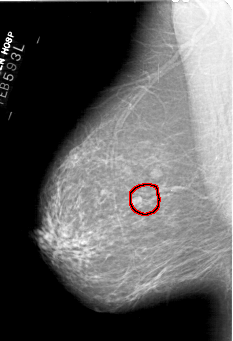

A_1443_1.LEFT_CC

LEFT_CC LINES 6571 PIXELS_PER_LINE 4036 BITS_PER_PIXEL 12 RESOLUTION 43.5 OVERLAY

FILE: A_1443_1.LEFT_CC.OVERLAY

TOTAL_ABNORMALITIES 1

ABNORMALITY 1

LESION_TYPE MASS SHAPE OVAL MARGINS ILL_DEFINED

ASSESSMENT 4

SUBTLETY 3

PATHOLOGY BENIGN

TOTAL_OUTLINES 1

BOUNDARY